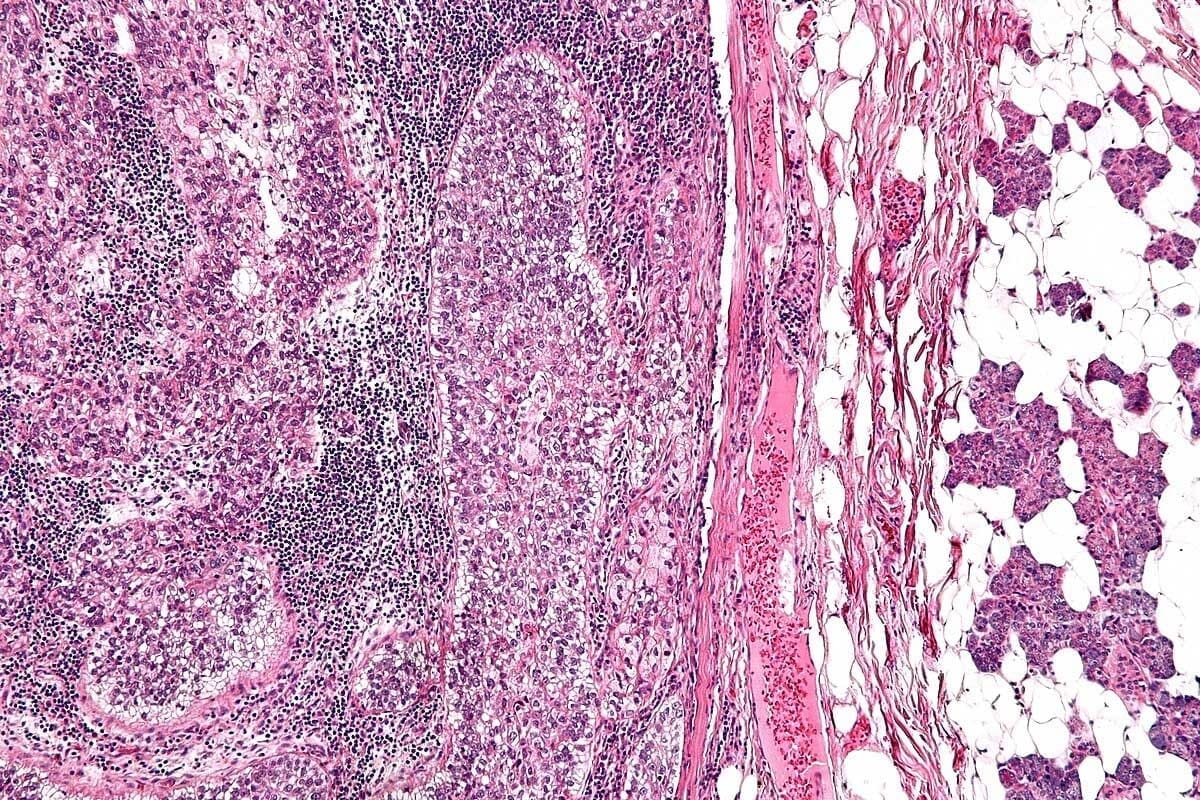

Myelodysplastic Syndromes (MDS)

Myelodysplastic syndromes (MDS) are a group of blood disorders. They happen when the bone marrow can’t make healthy blood cells. This can cause anemia, infections, and bleeding problems. Knowing about MDS is key to managing it and improving life quality.

Classification of MDS

MDS is sorted by the blood cells affected and how severe it is. The World Health Organization (WHO) classification helps figure out the prognosis and treatment. There are different types, like refractory anemia and refractory anemia with ring sideroblasts.

Doctors look at blood and bone marrow samples to classify MDS. This is important for choosing the right treatment.